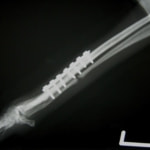

症例3:キルシュナーワイヤーのピンニングによる整復

ペルシャ猫 11ヶ月齢 雄

他院にて左大腿骨遠位の成長板骨折(salter-harrisⅠ型)が認められており、治療相談を目的として来院。当院にて、キルシュナーワイヤーを用いたピンニングにより骨折部位の整復を行いました。術後の経過は良好で、現在も経過観察中です。

術前レントゲン

術後レントゲン

機器

Arthrex社のターゲティングデバイスを用いてピンニングの位置を調整することで、確実な固定を行っています。当院ではこの手術器具以外にも、人の手術にも使用される様々な器具を導入し、手術精度を高め、また医療メーカーと新しい器具の開発、試作にも取り組んでおります。